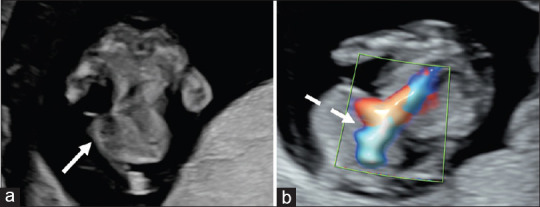

A Pattern of Malformations in the First Trimester Ultrasound.